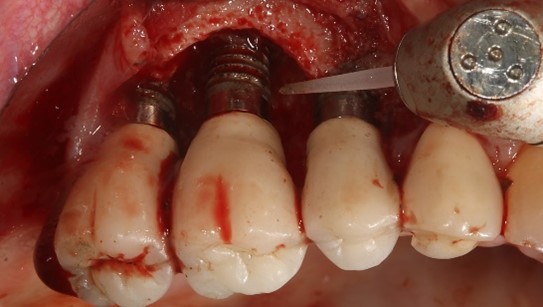

• un traitement comprenant un débridement mécanique, suivi d’un aéropolissage poudre d’air avec de la glycine (fig. 7), suivi d’un conditionnement d’acide citrique ou d’eau oxygénée à 10 volumes avec un rinçage vigoureux de la surface implantaire à l’eau stérile après chaque étape, serait capable de décontaminer la surface infectée. (Rosen et al 2018)

Figure 7: aéro polissage de la surface implantaire à l’aide d’une tête fine (Prophyflex Kavo), après élimination du tissu de granulation